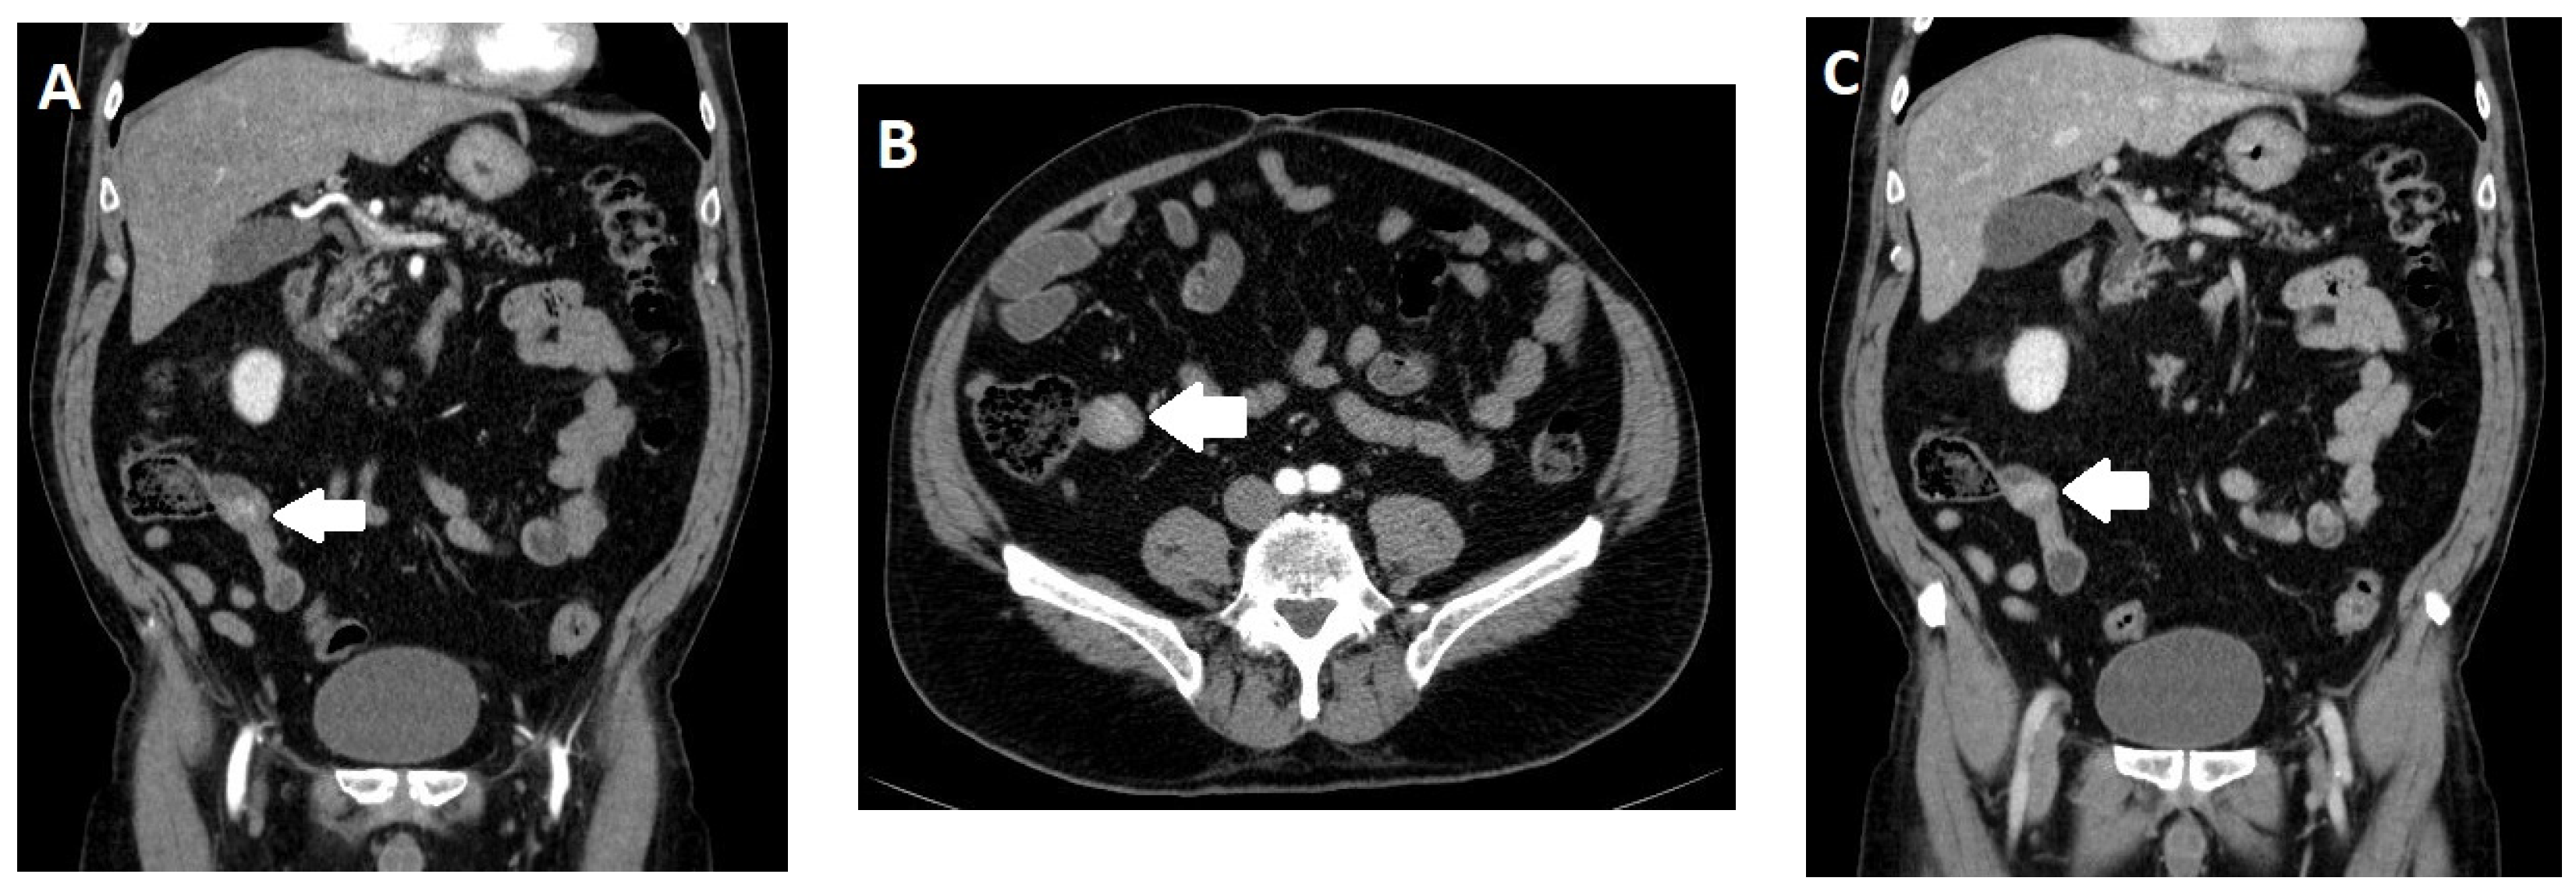

2.4. Imaging

- Pilleul, F.; Penigaud, M.; Milot, L.; Saurin, J.C.; Chayvialle, J.A.; Valette, P.J. Possible small-bowel neoplasms: Contrast-enhanced and water-enhanced multidetector CT enteroclysis. Radiology 2006, 241, 796–801. [Google Scholar] [CrossRef]

- Soyer, P.; Dohan, A.; Eveno, C.; Dray, X.; Hamzi, L.; Hoeffel, C.; Kaci, R.; Boudiaf, M. Carcinoid tumors of the small-bowel: Evaluation with 64-section CT-enteroclysis. Eur. J. Radiol. 2013, 82, 943–950. [Google Scholar] [CrossRef]

- Dohan, A.; El Fattach, H.; Barat, M.; Guerrache, Y.; Eveno, C.; Dautry, R.; Mule, S.; Boudiaf, M.; Hoeffel, C.; Soyer, P. Neuroendocrine tumors of the small bowel: Evaluation with MR-enterography. Clin. Imaging 2016, 40, 541–547. [Google Scholar] [CrossRef]